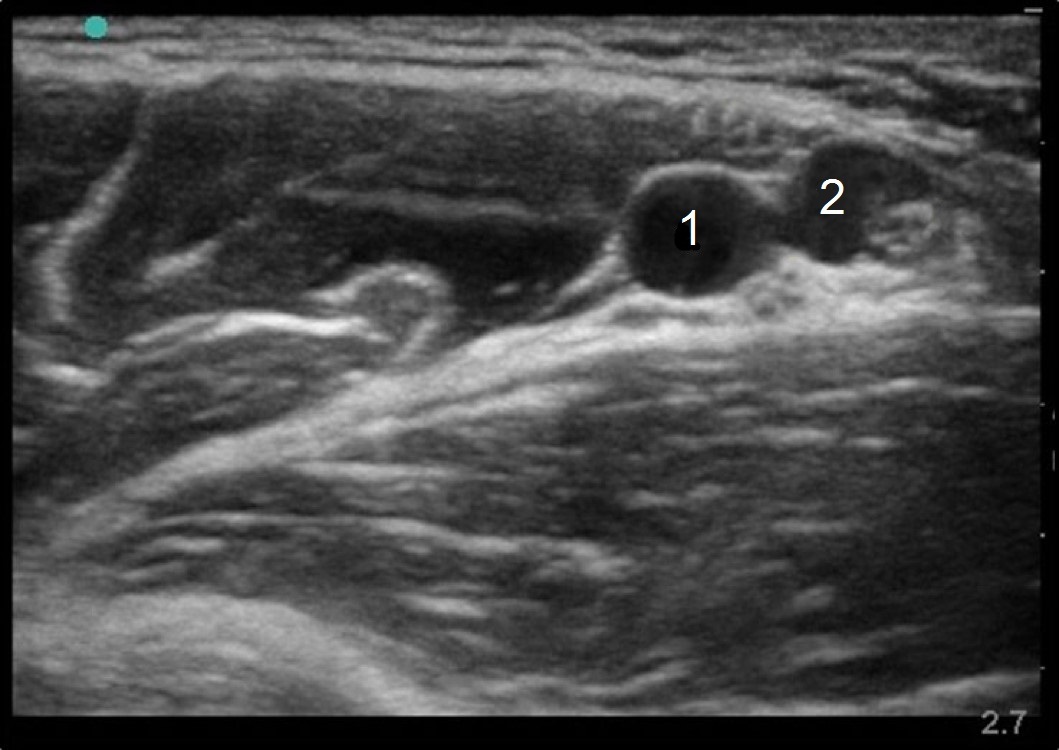

Axillary Vessels Anatomy Image

Axillary Artery

Axillary Vein